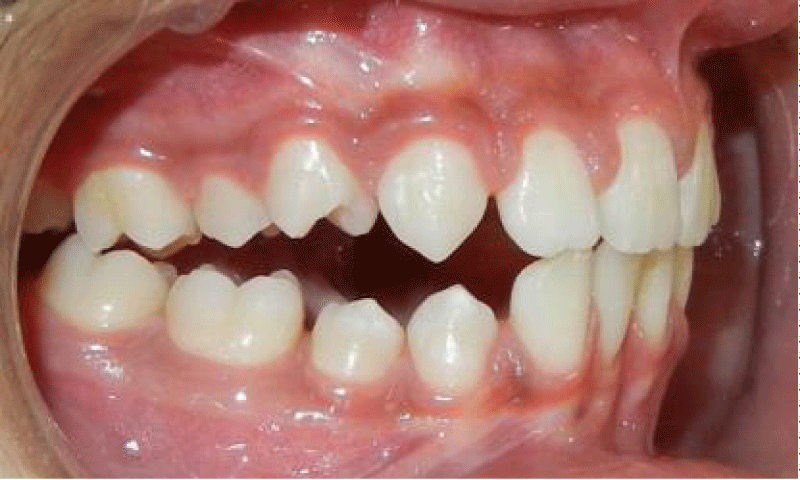

前开咬

它被定义为没有接触前地区的咬合不正的牙齿拱门,(图1)和后牙咬合。它叫做结合开放咬当咬合不正延伸到后段[7]。